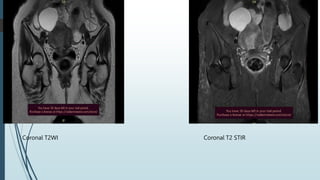

Coronal T2WI Coronal T2 STIR

 Uterus is bulky with diffuse junctional wall widening upto 13 mm

 Uterus shows homogenous post contrast enhancement. No

diffusion restriction seen in that widened junctional zone.